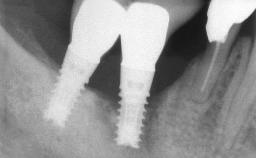

Management of a Fractured Implant Supporting a Screw-retained Metal-ceramic Restoration

The fracture of an implant after it has been restored is one of the most severe complications. It most frequently occurs in partially edentulous jaws (1.5%). Most implant fractures involve implants with a diameter of 3.75 mm made of commercially pure titanium (Eckert 2010). Unfortunately, many cases are not reported or documented by the clinicians involved in resolving the problems created by the fracture. This case report describes the management of an implant fracture at site 36 in a middle-aged male patient. The implant had been restored with a screw-retained metal-ceramic crown.